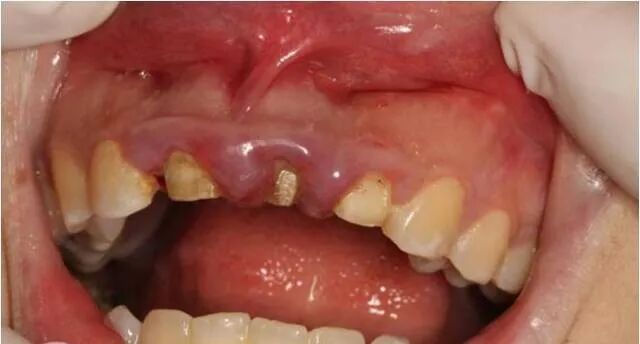

术后两周拆线后口内情况

三个月后修复牙体制备后

固定修复后口内像

修复前后对比图